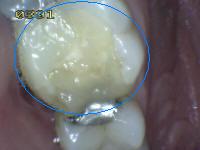

1 |

Sellador parcial |